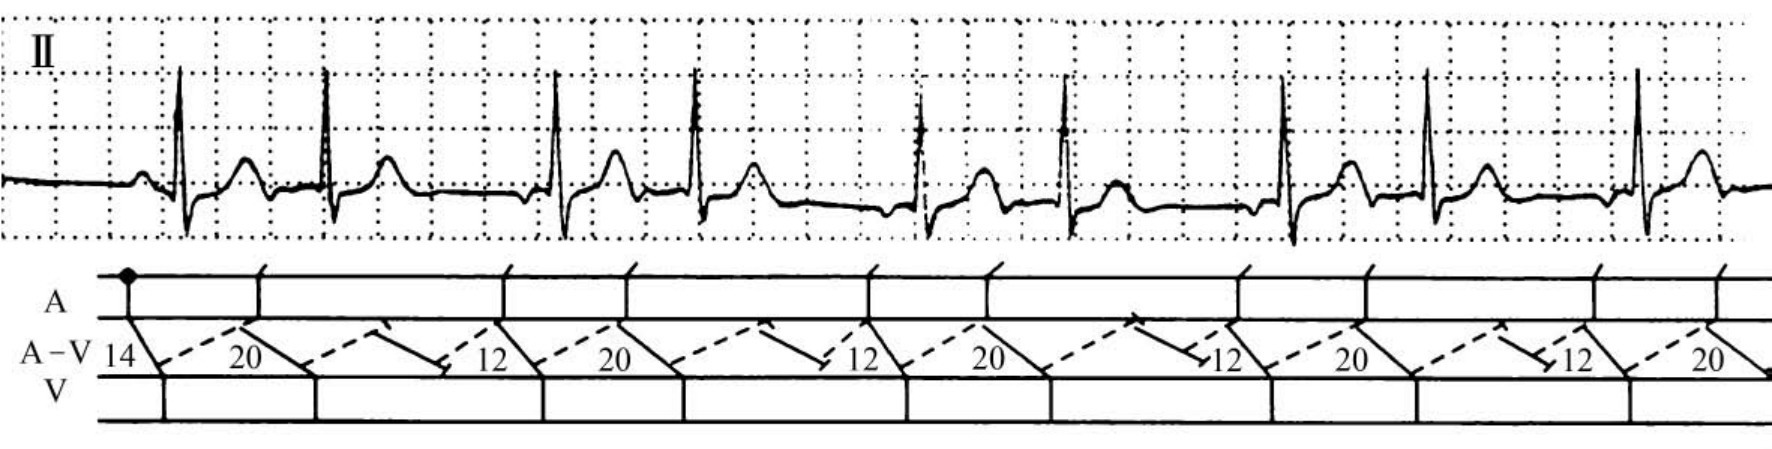

图37-15 快—慢型房室结折返性心动过速伴双径路3∶2同步文氏现象

患者男性,21岁,临床诊断:病毒性心肌炎。图示Ⅱ导联,第1个心搏为窦性,激动沿快径路下传心室,又沿慢径路逆传回心房,再沿快径路折回心室,形成折返性激动。当继续折返时,快慢径路皆同步发生阻滞,亦同步发生心房和心室漏搏,在房室结内形成“隐匿性折返”。形成房室同步漏搏的原因是房室结内快慢径路同步发生3∶2文氏型阻滞